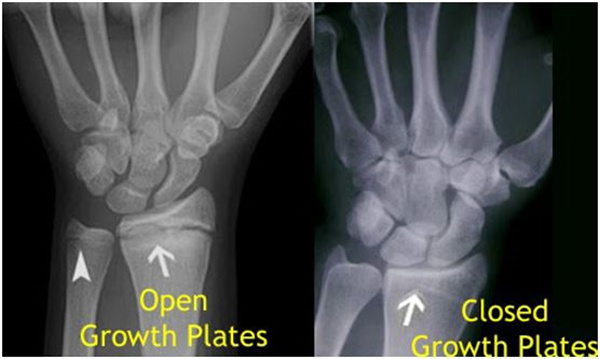

其实想要了解孩子的生长发育情况或者说孩子未来身高的趋势,测骨龄是个好办法。临床上通常拍摄儿童的左手正位X光片 , 采用《中华-05》骨龄标准对手腕骨发育程度进行骨龄评价。

我们都知道,人体的高矮是由骨骼的生长发育决定的,特别是下肢长骨。长骨呈长管状,在长骨的两端有一种专管骨骼生长的骺软骨,它与干骺端之间有一盘状软骨结构称为骺板(线),在幼儿的X光片上表现为一条较宽的透光带。(见下图)

未成年时随着年龄的增加骺软骨端不断骨化,骨骼就不断增长。当骨骺线完全闭合时骨骼就停止生长,个子也就不再增长了。一般骨骺端完全闭合的年龄是18~20岁左右。